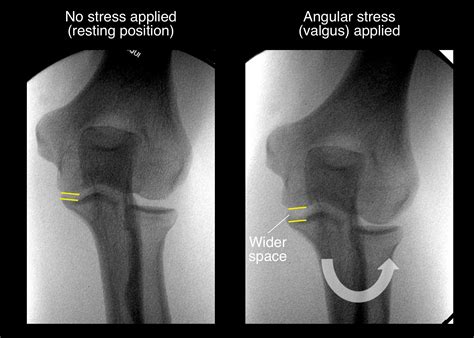

TOMMY JOHN SURGERY — Dr. Peter Johnston